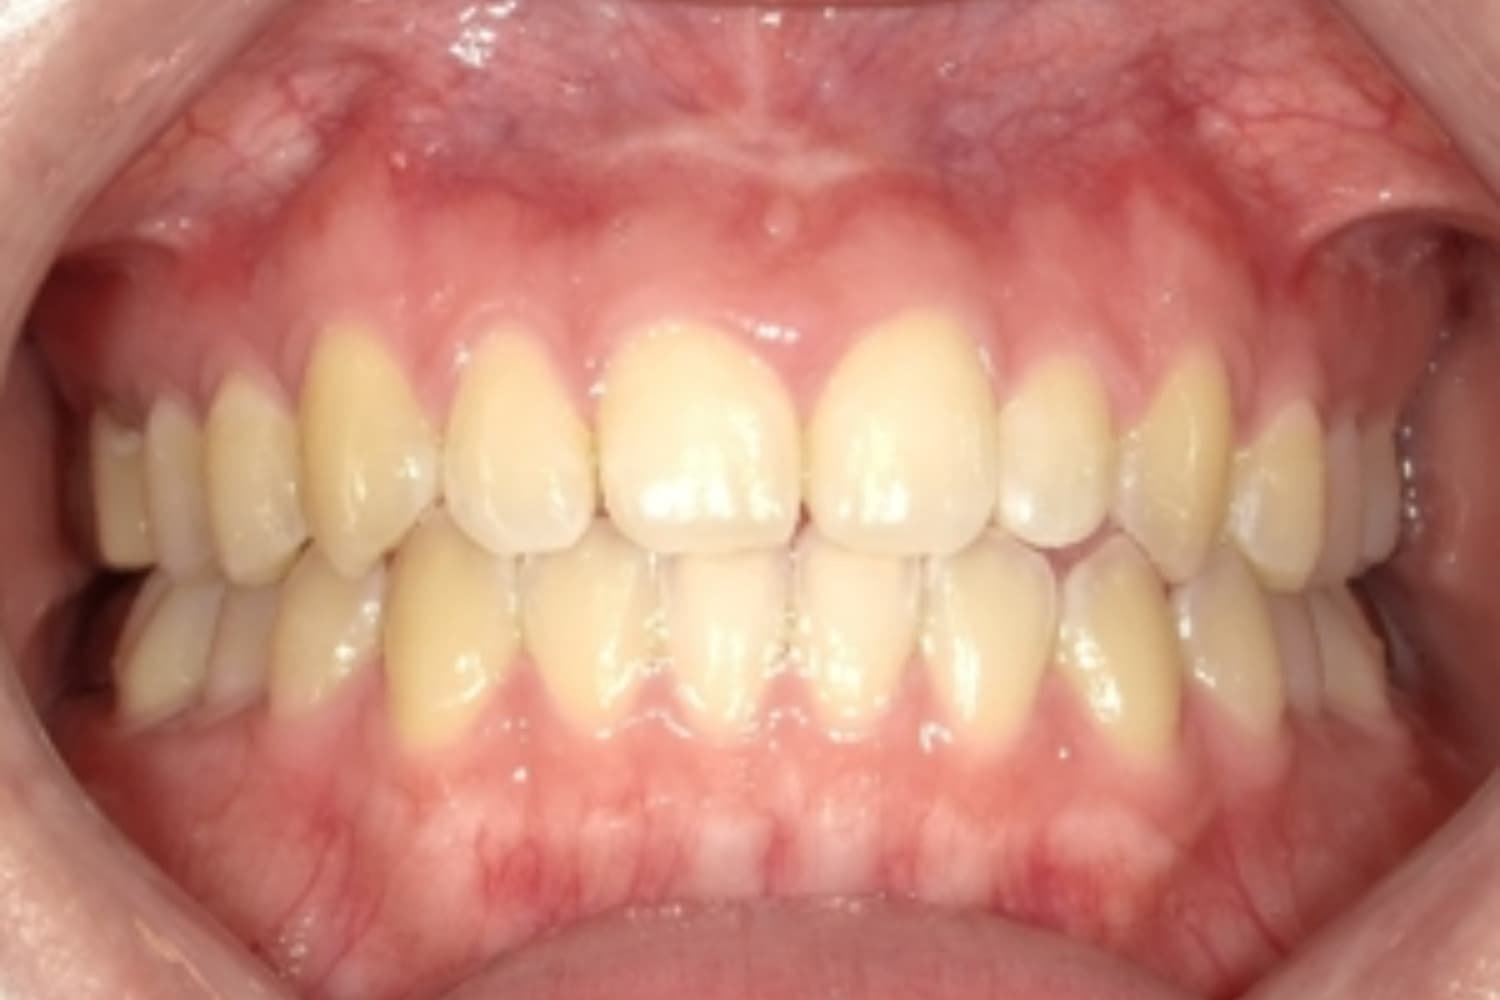

すきっぱ(空隙歯列)2

Before

After

気になる前歯の隙間と前歯のガタガタをマウスピース矯正(インビザライン)にて治療

治療期間

1年

費用

88万円(税込)